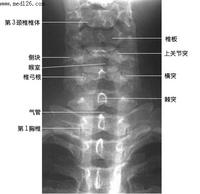

楼主所指的枢椎棘突密度减低区属正常表现,你可能多拿几个颈椎侧位片看看。

下面是我刚从网上下载的几张颈椎图片。